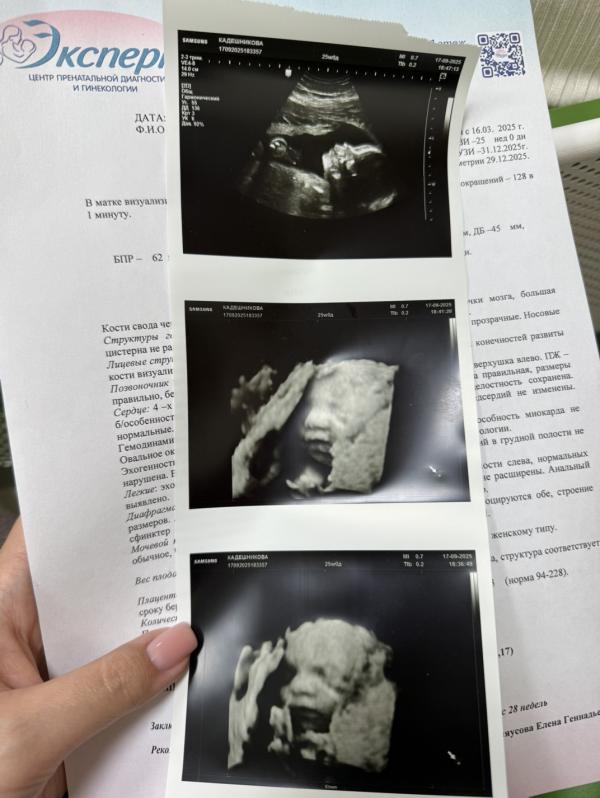

Врач все очень тщательно проверяла, несколько раз показывала нам каждый орган с разных сторон. А роговица до сих пор будет сниться мне в кошмарах 😄

А на 3D увидели личико, как сказала врач: жировой прослойки еще нет, но щечки уже появились. Вся в мать 😂

Сладкий пупс 😍.